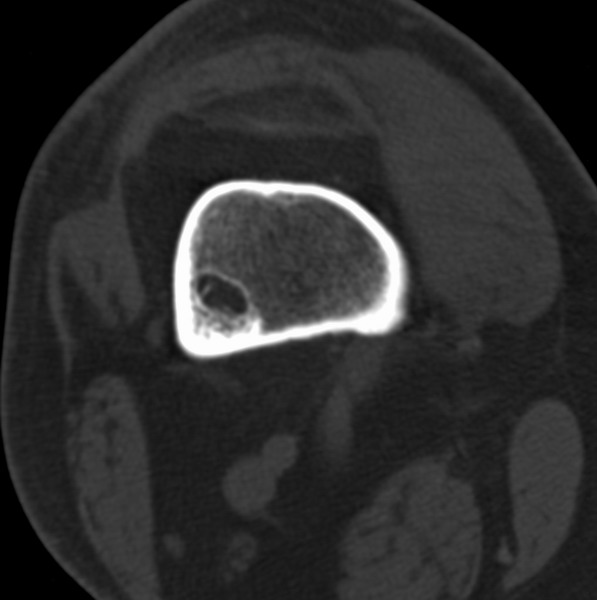

右侧膝关节疼痛一月

男、48

股骨下段、胫骨上段。

1、股骨干骺端病变考虑干骺端纤维性皮质缺损愈后(非骨化性纤维瘤)改变,胫骨近端内生骨瘤(或干骺端纤维性皮质缺损愈后改变);

2、骨关节炎,骨质增生,股骨外侧髁退变性囊肿(关节面软骨下囊肿);

3、髌骨前缘裂纹骨折?